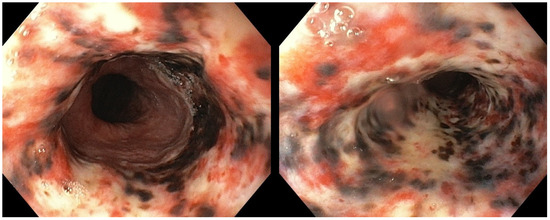

Post-operative stay was uneventful. Following the normal intestinal canalization and a clinical and laboratory improvement, on day 5, oral diet was gradually resumed. On day 7, EGD was repeated, showing nearly complete healing of the AEN, with only mild hyperemia and congestion at the medial and the distal esophagus, in the absence of strictures or other complications (Figure 3). Esophageal biopsies were taken, evidencing mild epithelial non-specific inflammation only. The patient was discharged home on day 8, and no complications were observed up to the 6-month follow-up.

Figure 3.

Follow-up esophagogastroduodenoscopy showing a nearly complete resolution of the esophageal necrosis, with mild hyperemia and congestion at the level of the middle and the distal esophagus.